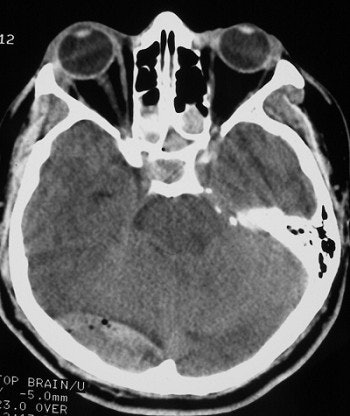

![]() |

| The above illustrates an epidural hematoma in the posterior fossa (right), secondary to a fracture of the skull base. Epidural hematomas are typically due to arterial bleeding between the surface of the brain and the skull. However, in this case the fracture is adjacent to the transverse sinus and is likely due to venous bleeding. This can be seen following blunt trauma to the head. |